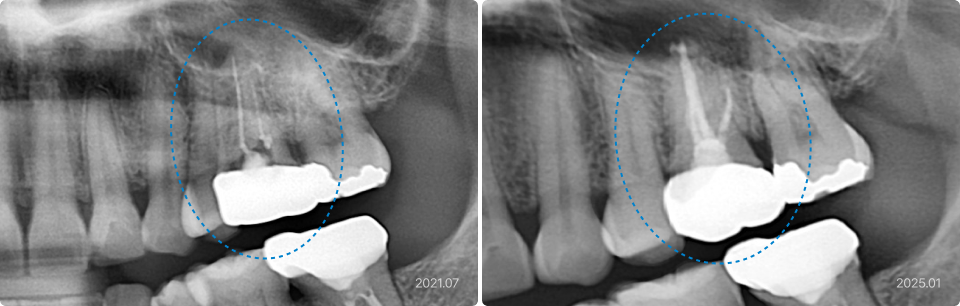

01

숨은 신경관까지 찾아 자연치아를 살린 재신경치료

치료 전

치료 후

치료 내용

• 크라운 안쪽으로 2차 충치 발생 및 신경관 중 일부가 치료되지 않아 염증 발생

• 기존 크라운 제거 및 숨겨진 신경관까지 철저히 세척, 소독하여 재신경치료 시행

• 치료 1년 6개월 후 x-ray에서 골 파괴 부위 감소하고 염증이 해소된 것을 확인